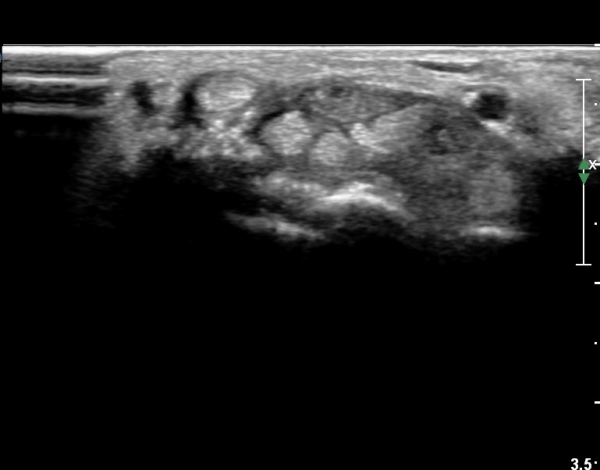

¼Õ¸ñ ºÎÀ§ Ⱦ´Ü¸é°Ë»ç¿¡¼ ¿ä°ñ°ú ¿ù»ó°ñ Àü¹æ¿¡ ¼®È¸È¼º À½¿µÀÌ Á¸ÀçÇϰí Àü¹ÝÀûÀÎ ¼öÁö ±¼°î°ÇÀÇ ºñÈÄ, Á¤Á߽ŰæÀÇ ºÎÁ¾°ú

ÈûÁÙ ¹× Á¤Á߽ŰæÀÇ Ç¥ÃþÀ¸·Î ÀüÀ§°¡ °üÂûµÈ´Ù, (»çÁø 1 ), ÆÄ¿öµµÇ÷¯°Ë»ç¿¡¼ Ç÷·ùÁõ°¡°¡ °üÂûµÊ´Ù(»çÁø 2)..